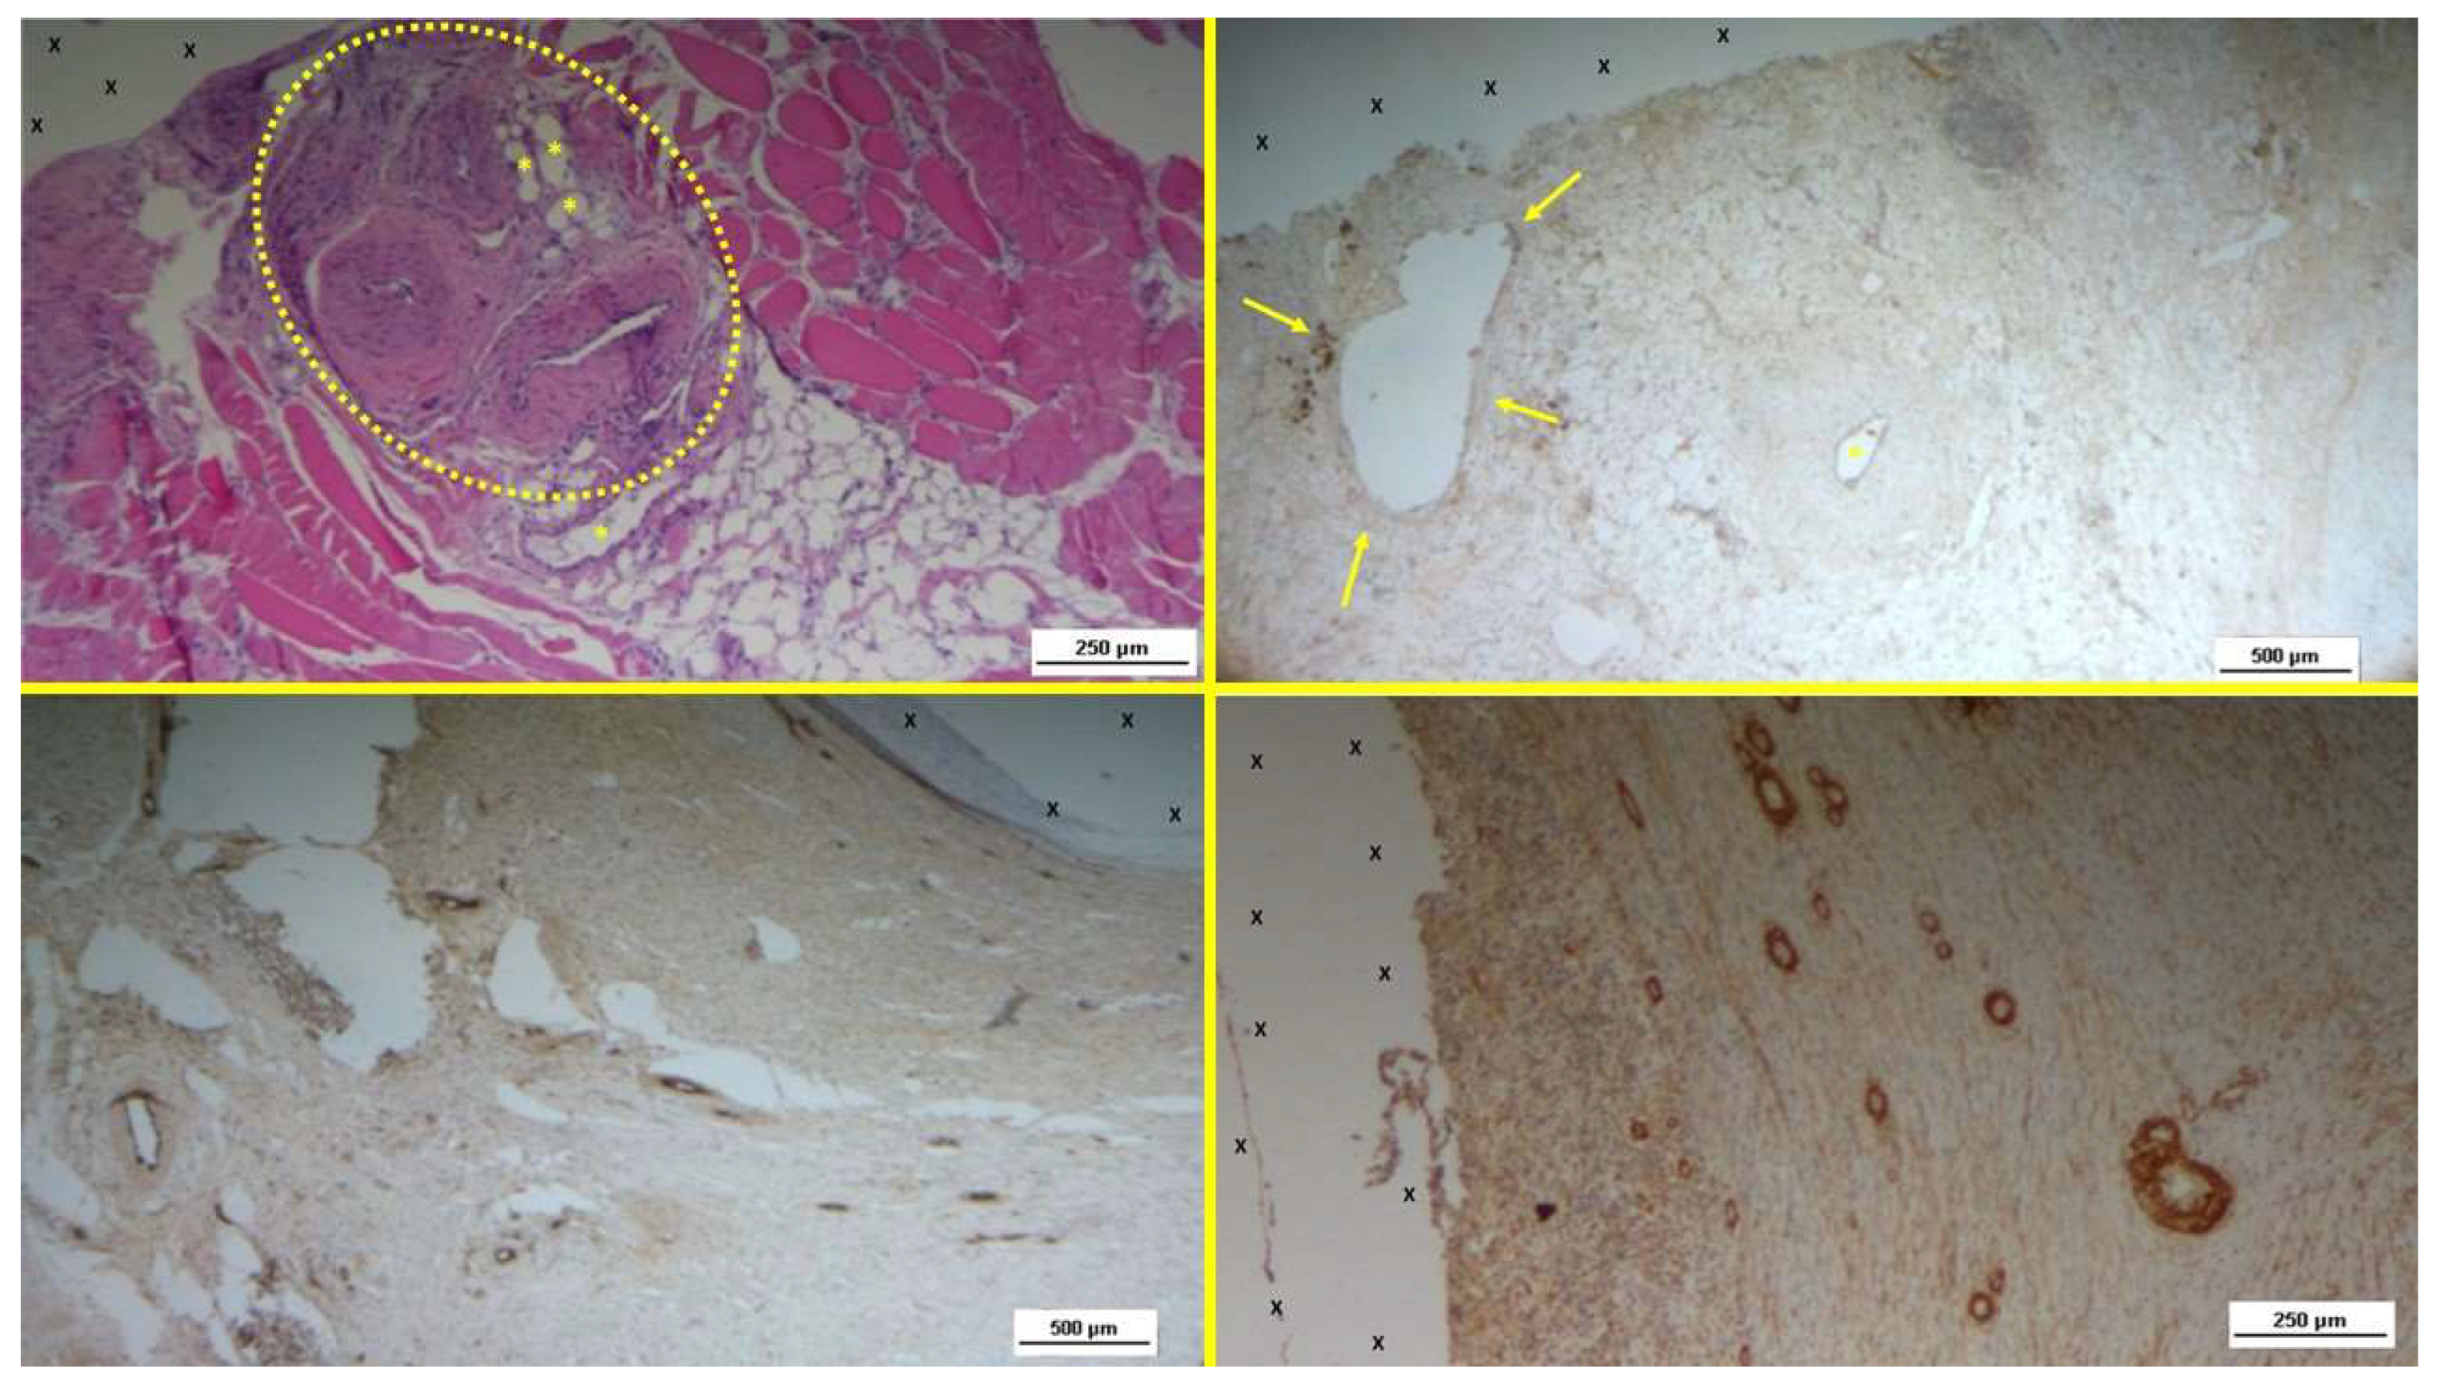

Figure 5.

- A: Biopsy sample removed 6 months post-implantation (Long term - LT). Well-formed convoluted arteries with thick muscular layers (yellow circle) and some veins (*) are embedded within newly developed muscle tissue (red) and adipose cells (white spots) surrounding the TPE scaffold (X). No inflammatory response is evident. HE 50X – B: Biopsy specimen excised from the S&S device 7 months post-implantation (Long term – LT). VEGF-positive elements compose the endothelial layer of a large vein (yellow arrows) and one artery (*) close to the TPE fabric of the 3D scaffold (X). VEGF 25X – C: Biopsy specimen excised 6 months post-implantation (Long term - LT). Mature endothelial elements of vessel structures (brown staining) are visible close to the TPE scaffold (X). CD31 50X – D: Biopsy specimen excised 7 months post-implantation (Long term - LT). Thick muscular layers (stained in brown) of vascular elements are evident near the TPE fabric of the 3D scaffold (X). SMA 50X.